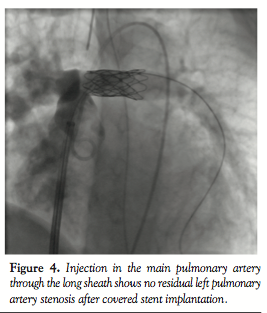

further delineate the anatomy. Ascending aortic angiogram showed significant opacification of the PAs (Figure 3). The aortopulmonary window could be crossed easily from the PA into the aorta by advancing a wedge catheter with the balloon inflated; hence, its diameter was above 1 cm. It was decided not to balloon-size the defect, because of the possibility of further increasing its size. Therefore, a 34-mm long covered stent that was premounted on a 16-mm diameter balloon was chosen and implanted at the exact point of the window, sealing it off and at the same time relieving the left PA stenosis (Figures 4 and 5).